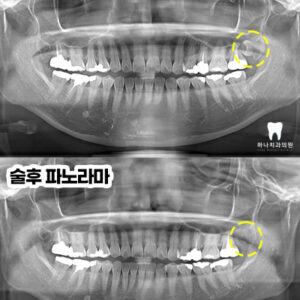

울산삼산동치과 매복된 사랑니 발치와 임플란트 수복(대합치 형태 회복) 안녕하세요! 하나치과입니다~:) 백세 시대라 불리는 요즘, 오복 중 하나로 여겼던 치아의 기능은 삶의 질을 좌우하는 요소가 될 수 있는데요. 현대사회에 들어서면서 잘못된 식습관과 치아 건강 관리로 노령층의 전유물로만 여겼던 임플란트가 젊은 연령층에서도 증가하고 있습니다. 치과 치료에 대한 두려움이나 시간, 더보기…